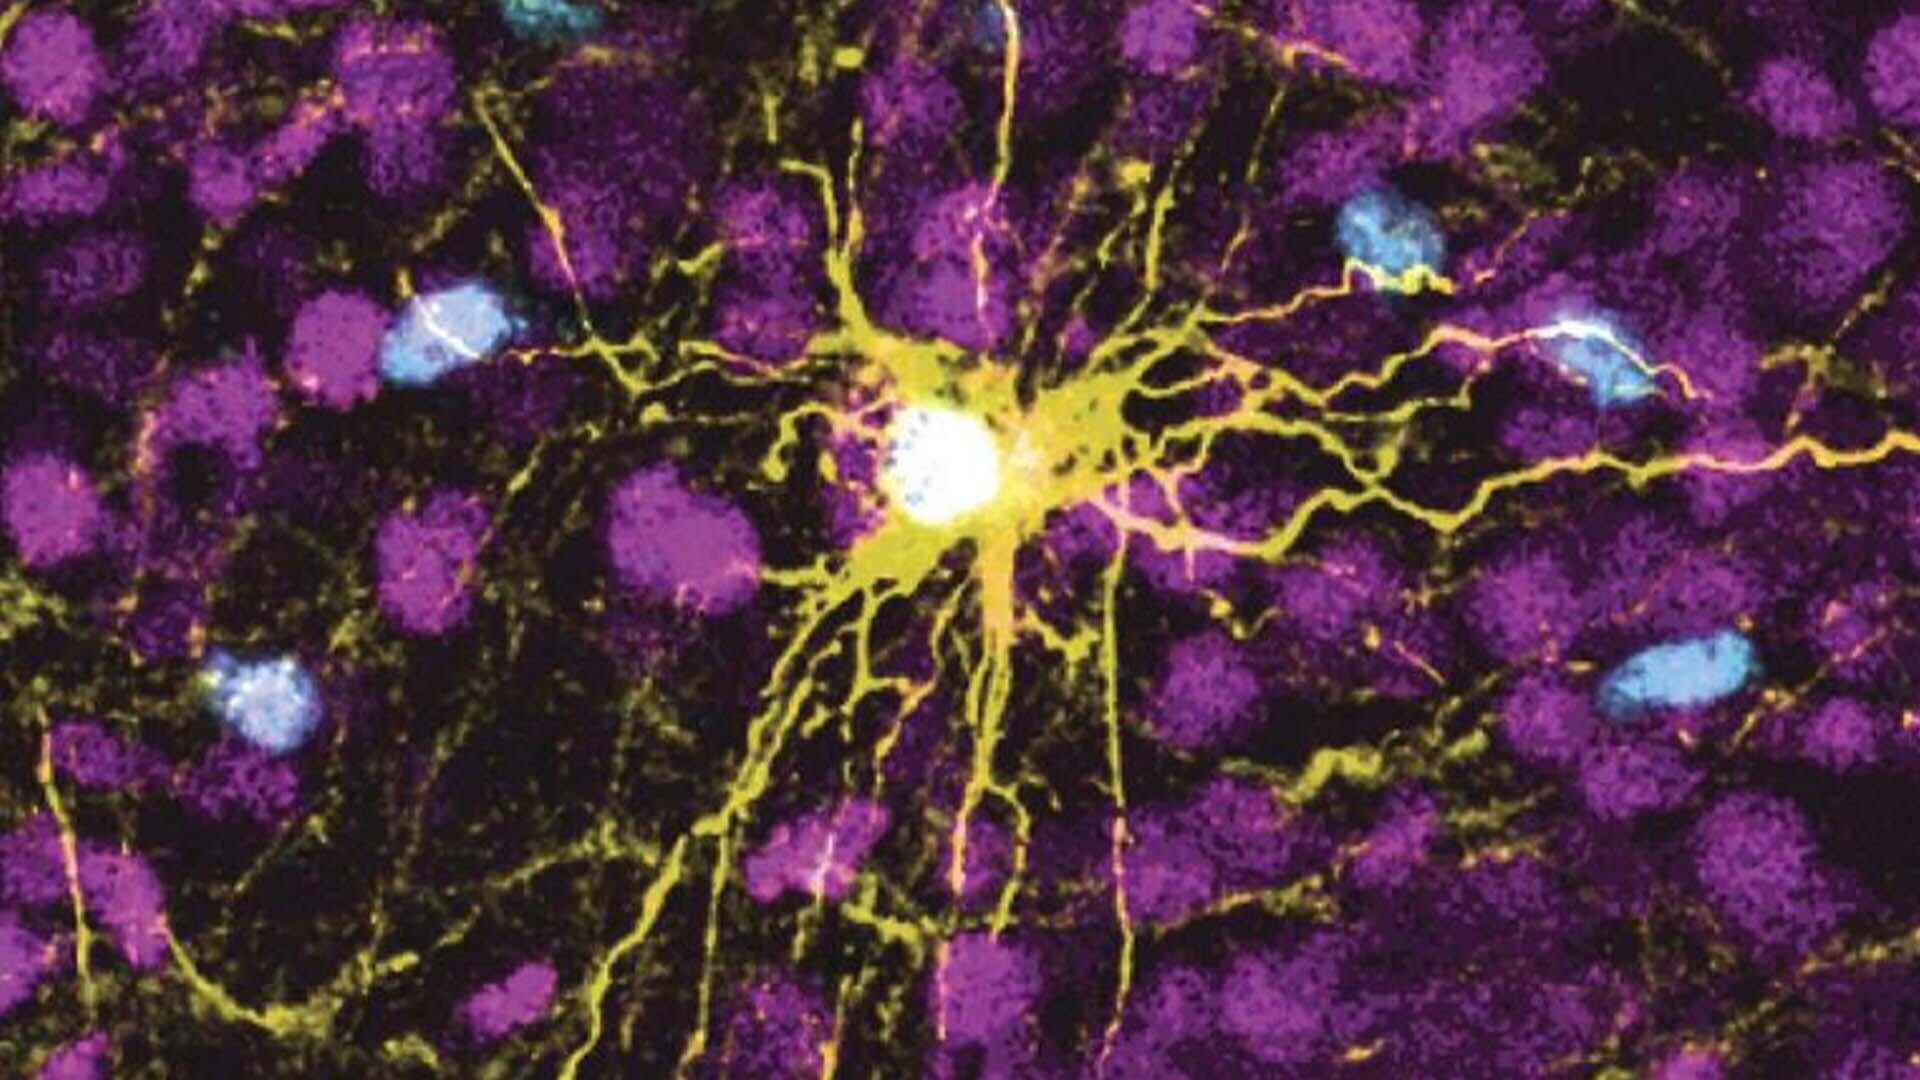

Il est de notoriété publique que la partie droite du cerveau contrôle la partie gauche du corps, et vice-versa. De manière imagée, le syndrome du mouvement en miroir se produit lorsque le fil électrique qui part d'un côté du cerveau pour s'en aller vers l'autre côté du corps se dédouble et fait un détour du mauvais côté, provoquant ces mouvements involontaires.

Le professeur Charron, la docteure Myriam Srour de l’Hôpital de Montréal pour enfants et les chercheuses Sabrina Schlienger et Patricia Yam ont identifié un nouveau gène et un nouveau mécanisme responsables de ce dérèglement.

Ils ont été en mesure de reproduire, en laboratoire, le problème chez des souris modifiées génétiquement. Ces souris, a indiqué le professeur Charron, peinent à se déplacer normalement, par exemple quand on leur demande de marcher sur une échelle, ce qu'elles devraient être en mesure de faire assez facilement.